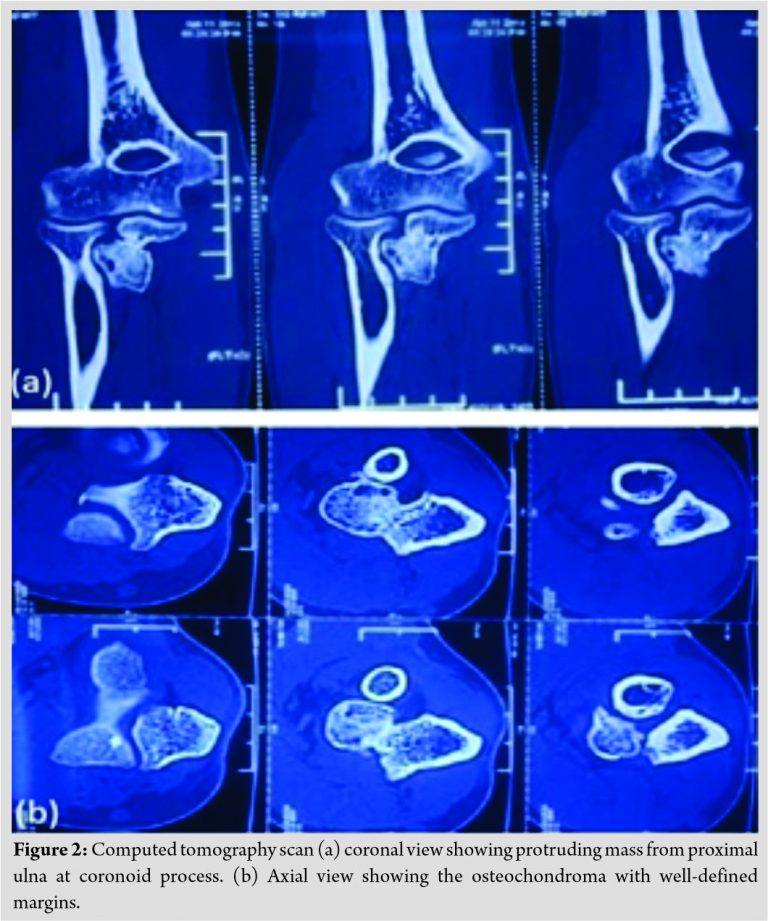

CT scan confirmed in detail the bony protuberance at the proximal ulna, which was solitary and did not involve any soft tissue (Fig. 2).